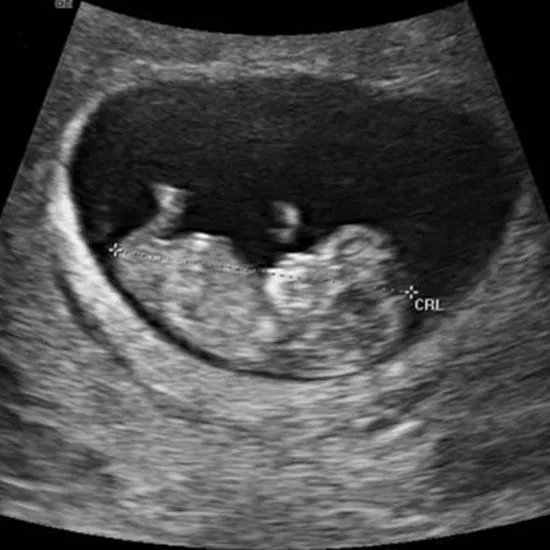

5. エコー写真と妊娠週数の関係

出生前診断を検討する時期は、初めて赤ちゃんのエコー写真をもらう時期と重なります。「妊娠8週のエコー写真」は、赤ちゃんの心拍がしっかり確認でき、手足の芽が見え始める感動的な時期です。

📸 妊娠週数別エコー写真の見え方

-

•

妊娠5~6週:胎嚢(赤ちゃんの部屋)が見えます。まだ赤ちゃん自身は見えないことが多いです。

妊娠7~8週:【検査検討のタイミング】心拍が確認され、「二頭身」の可愛い姿が見え始めます。この時期にNIPTなどの出生前診断について調べ始める方が最も多いです。

妊娠9~10週:人間らしい形になってきます。ミネルバクリニックでは、この9週0日から標準的なNIPT検査が可能です。